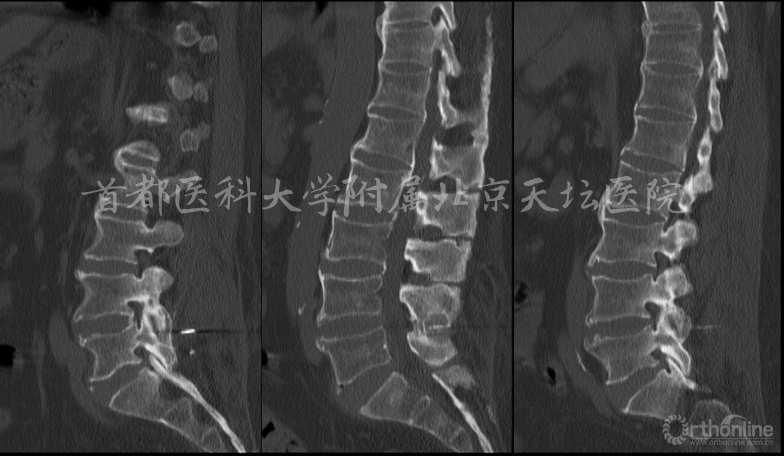

影像资料:

诊断:

• 腰椎管狭窄症(双侧神经根管狭窄)

• 棘突间植入物术后(Wallis)

• 棘突骨折

针对此病例,各位专家的讨论焦点主要落在棘突间植入物的疗效究竟如何上。天坛医院刘宝戈教授针对这个病例指出,患者曾在外院行棘突间植入物手术,术后不久再次出现症状,翻修手术如何进行?这需要细致的考量。针对该例老年患者,他们最终选择了微创的治疗方式,基于术前精确责任节段的定位,术后疗效满意。